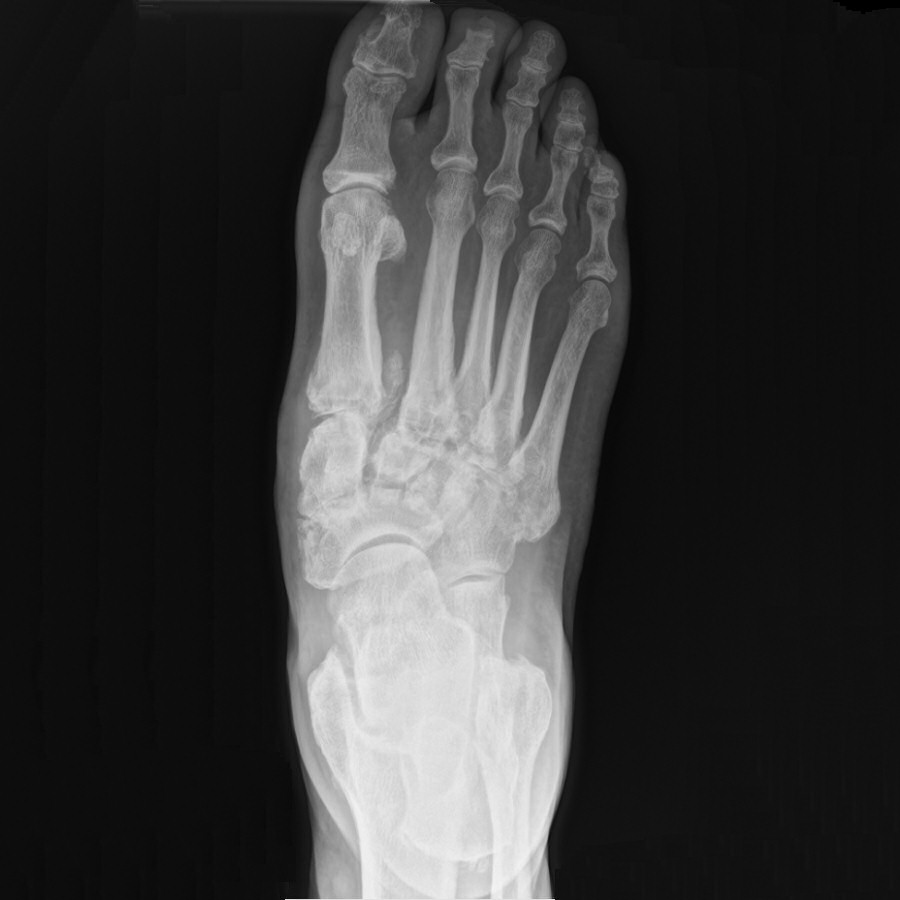

Obehandlad charcotfot, patienten noterade formförändring i fot ca 1 månad innan undersökning